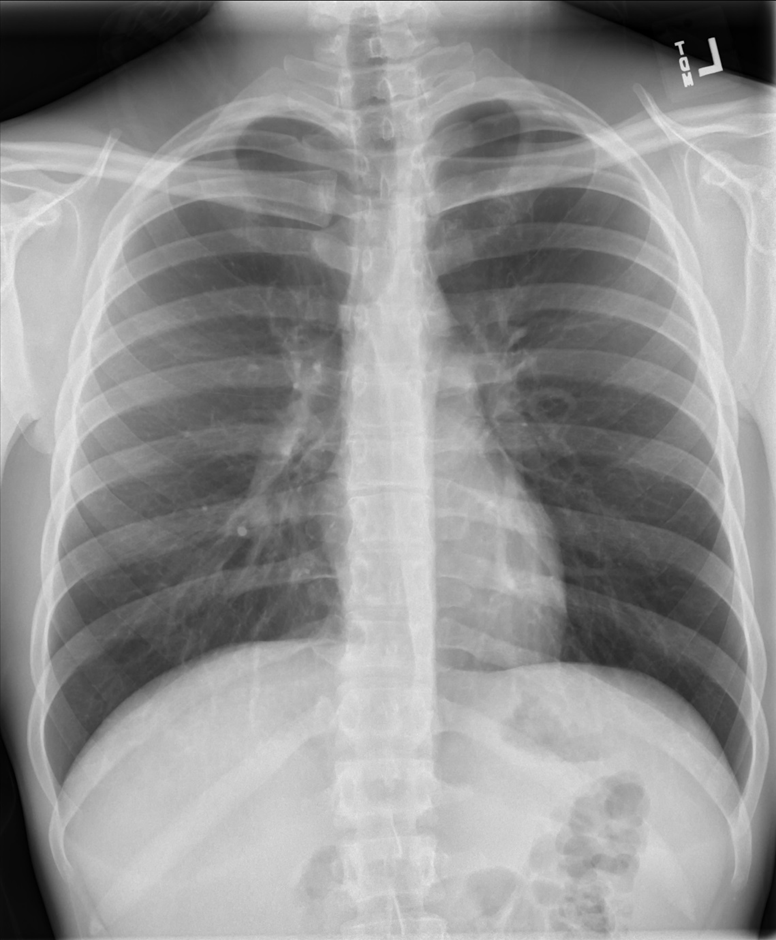

Chest Radiograph